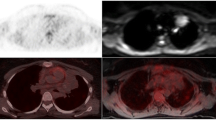

All of the 47 consensus interim and end of treatment examinations were scored similar on FDG PET/MR and PET/CT in terms of criteria of respons. Deauville score grading showed good agreement on weighted kappa, κ 0.72 (95% CI 0.54–0.89). Difference in Deauville score grading between PET/MR and PET/CT was seen in 11 patients and only in those with complete metabolic response (Deauville score 1–3). Figure 4 shows a patient with partial metabolic response and Deauville score 5 at end of treatment response on both image modalities, while the FDG avid lesion was scored as soft tissue on PET/CT but correctly identified in scapula on PET/MR.

A 71-year-old male with high-grade B-cell lymphoma stage IVA. End of treatment PET/CT in the upper row and PET/MR in the bottom row. The FDG avid lesion was scored as soft tissue on PET/CT and bone marrow on PET/MR. The lesion was localized in scapulae in the MRI sequences T2-HASTE, DWI (b800), ADC map, and T1Dixon in phase. Deauville score 5 and partial metabolic response on both modalities

In response assessment scans, we found a sensitivity of 100% and a specificity of 99.9% for FDG PET/MR on both nodal and extranodal sites combined. Seven of the 43 response assessment scans had FDG avid disease present on both modalities. Among these patients, one patient with partial metabolic response on both examinations also had an axillary node that was graded positive on FDG PET/MR due to higher SUVmax than on PET/CT. In addition, one bone marrow was graded positive on FDG PET/MR and labeled as soft tissue on PET/CT (Fig. 4).